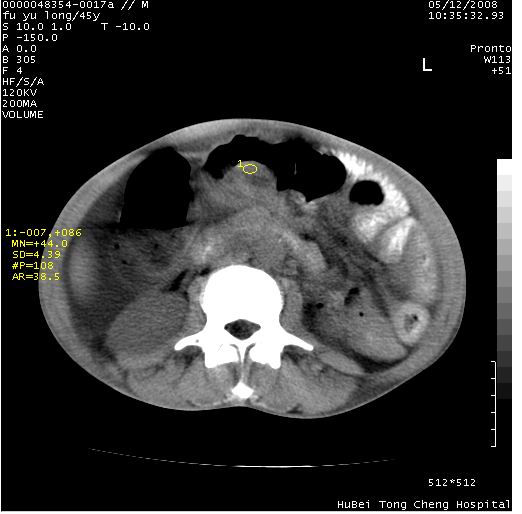

以下是引用医影拾贝在2008-5-30 2:38:00的发言:[br]气肿性胃炎、胃十二指肠溃疡、腹膜炎,考虑穿孔可能性较大

以下是引用lkc8963在2008-5-30 8:44:00的发言:[br]胃窦癌伴网膜(胃结肠韧带)/腹膜及腹膜后淋巴结转移.